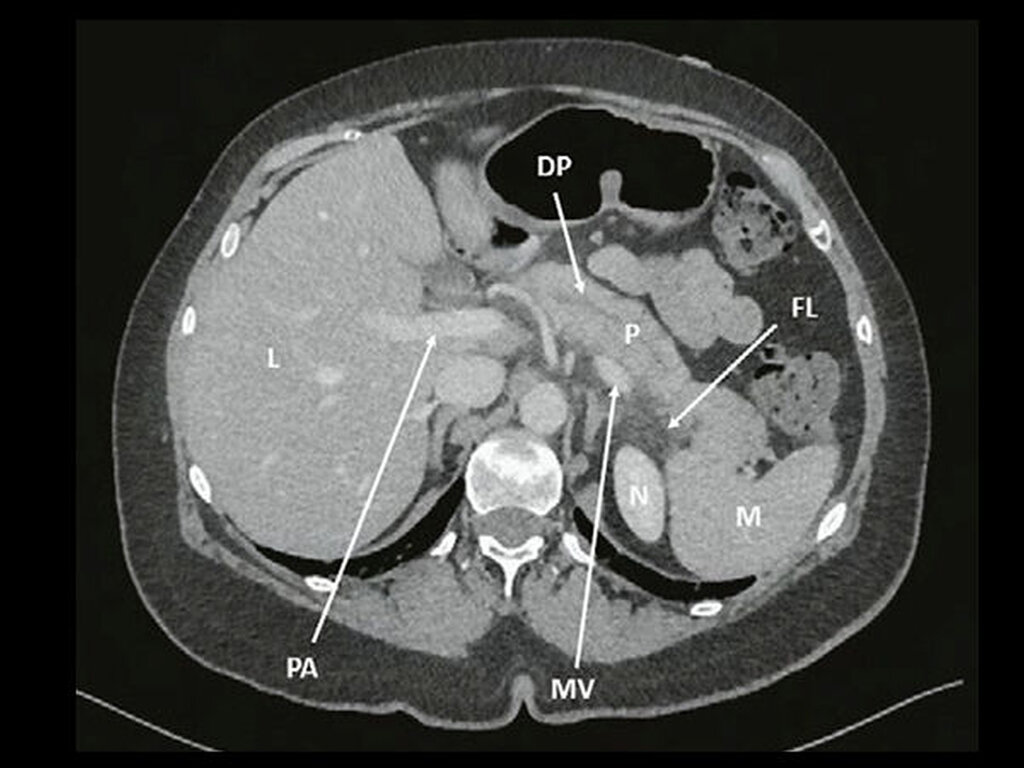

Eine 61-jährige Patientin mit einer postmenopausalen Osteoporose, einer Divertikulose, seit 2005 bekannten und im Verlauf größenregredienten Pankreaszysten sowie einer Allergie auf Neo-Citran® stellte sich aufgrund einer zwar relativ lokalisierten, gleichwohl aber schweren Parodontitis vor. Insbesondere die lateralen Inzisiven zeigten dabei Sondierungstiefen bis zu 9mm mit Suppuration/Bluten auf Sondieren (Abbildung 1 und 2), die bisher – trotz relativ guter Mundhygiene – bei verschiedenen Zahnärzten ohne Erfolg behandelt wurde.

Diese Befunde waren mit entzündlichen Veränderungen und somit mit der klinischen Präsentation und den Laborbefunden vereinbar. Aufgrund dieser Befunde wurde die Patientin auf der gastroenterologischen/viszeralchirurgischen Station des Inselspitals Bern zur weiteren Behandlung stationär aufgenommen. Unter Hydrierung, analgetischer Therapie sowie Nahrungskarenz stellte sich in der Folge eine Besserung ein und die Patientin konnte nach drei Tagen in gutem Allgemeinzustand nach Hause entlassen werden. Zahnmedizinisch zeigten die weiteren Recalls nach Initialtherapie erfreuliche parodontale Befunde, weshalb keine weiteren parodontalchirurgischen Therapien durchgeführt werden mussten (Abbildung 1 und 2).